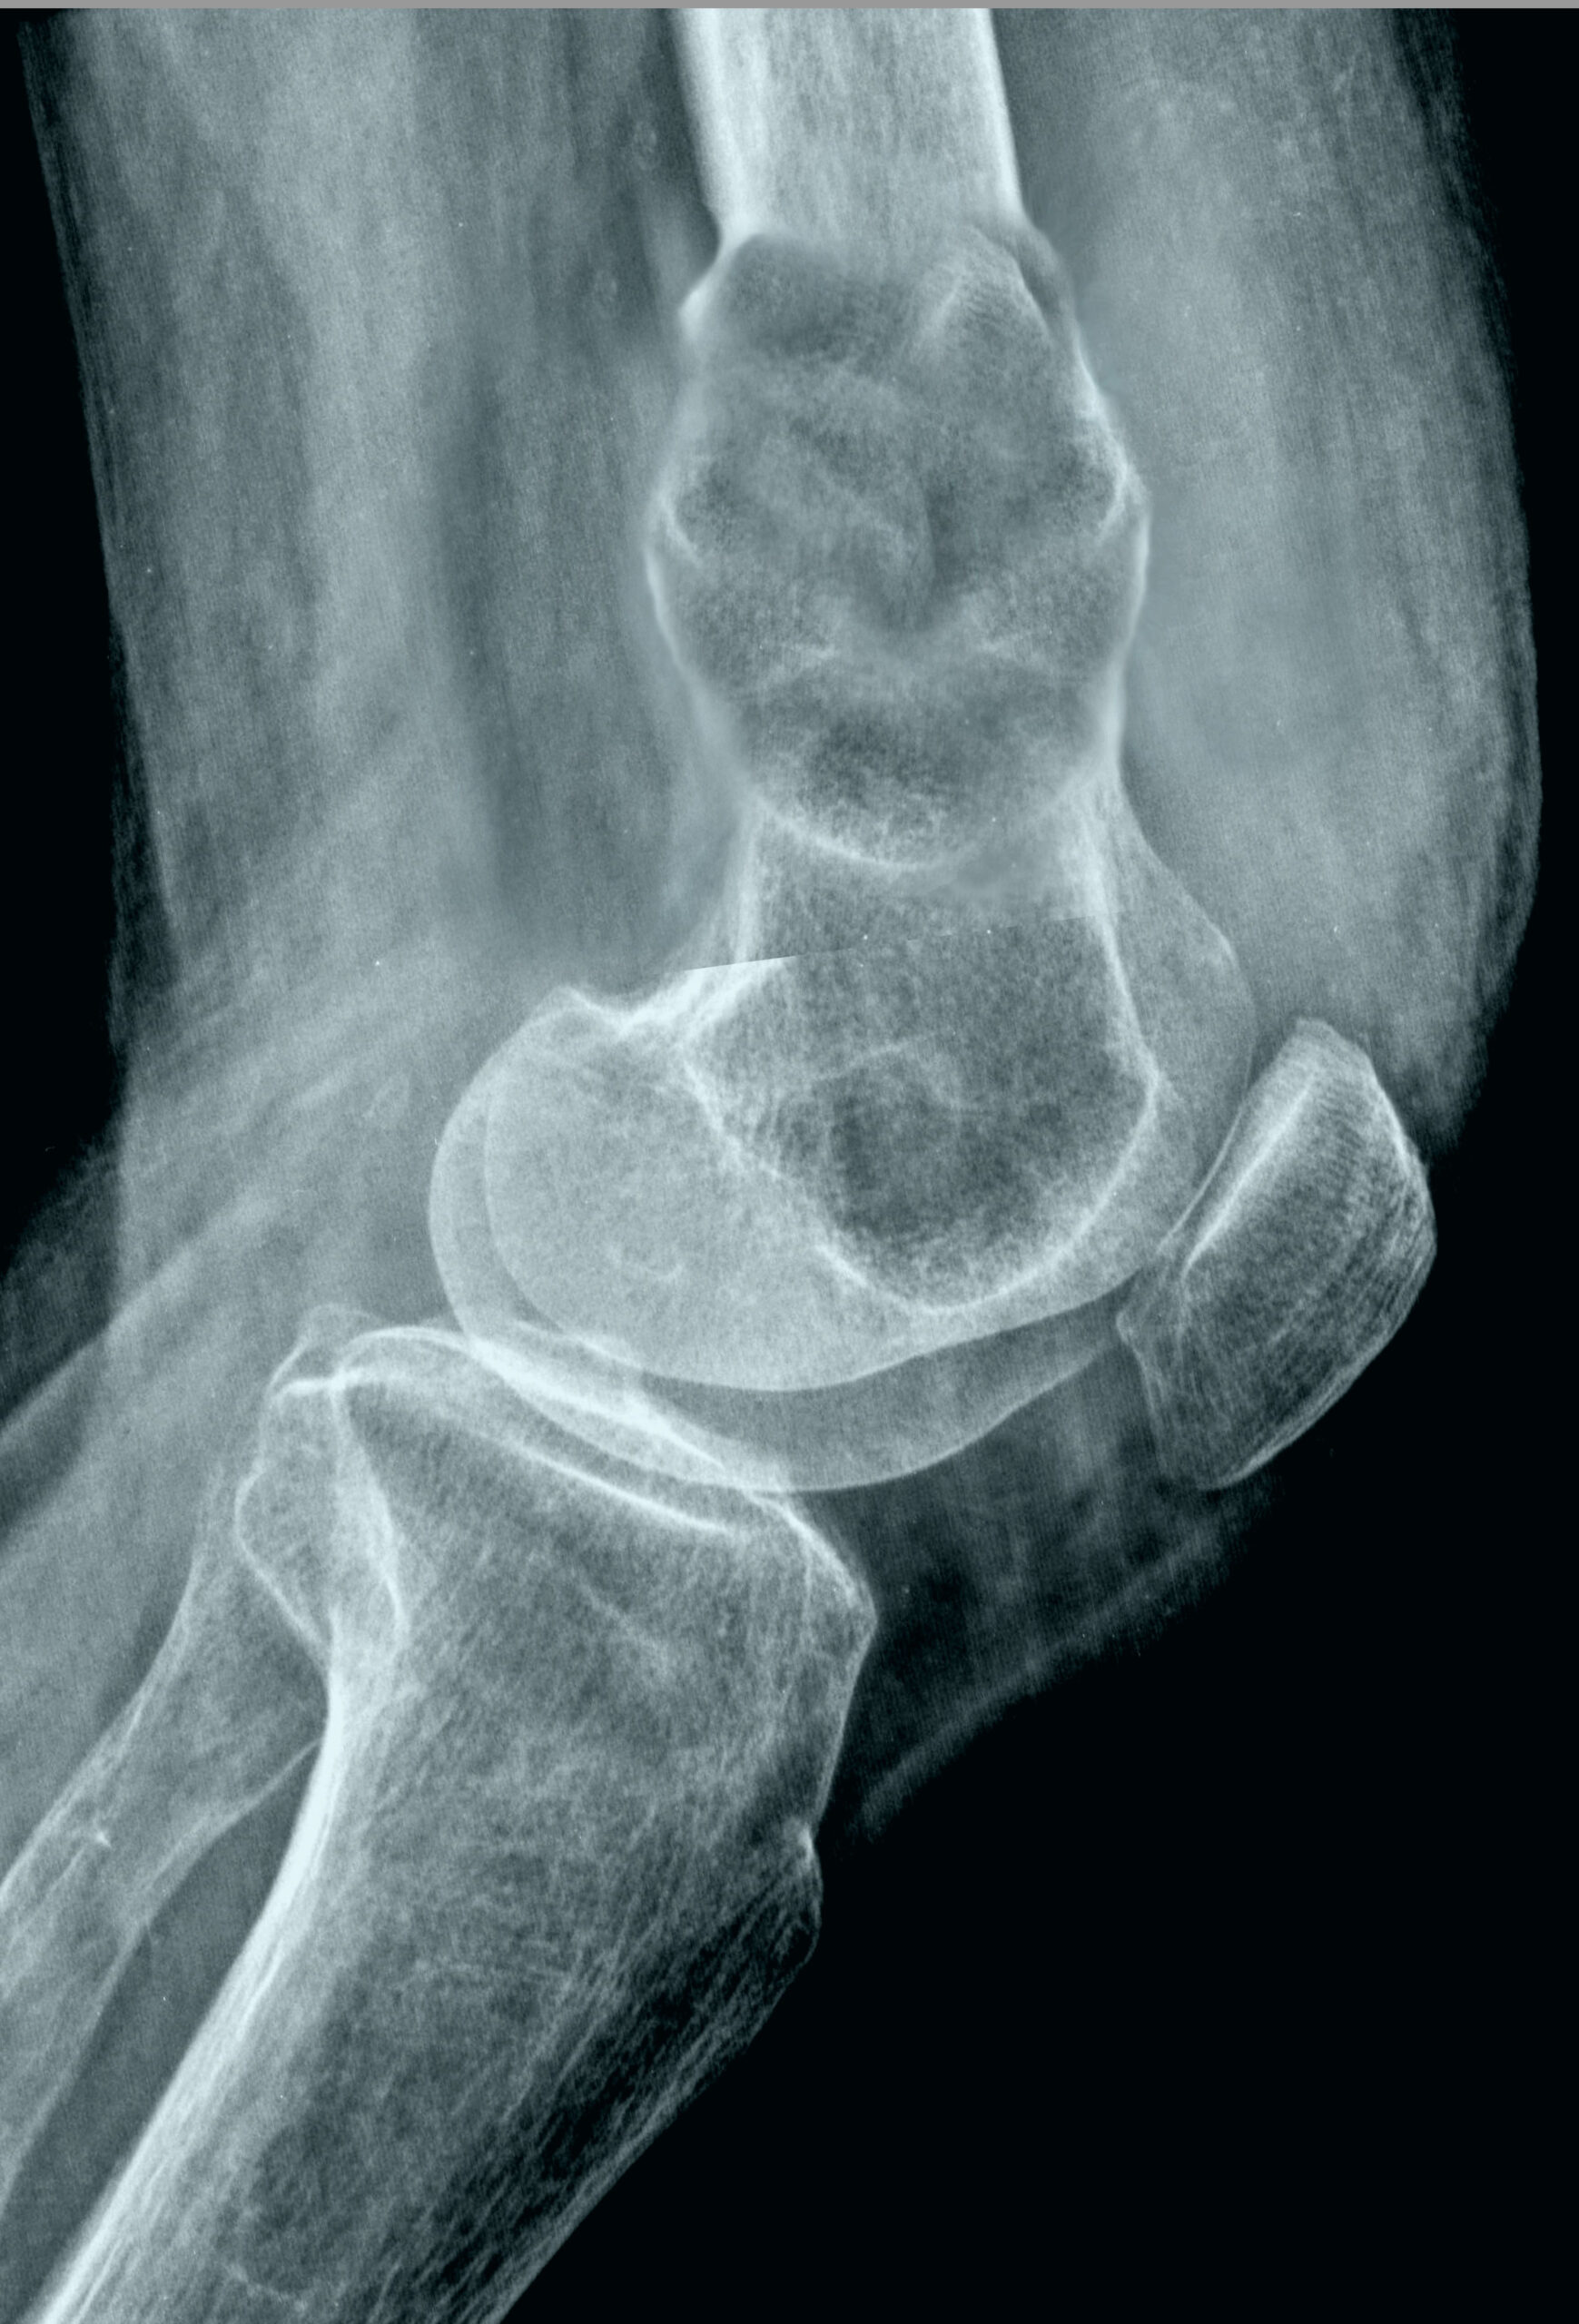

Diagnosis of hip cancer typically involves X-rays, MRI, and biopsy. This process is essential for creating an effective treatment plan.